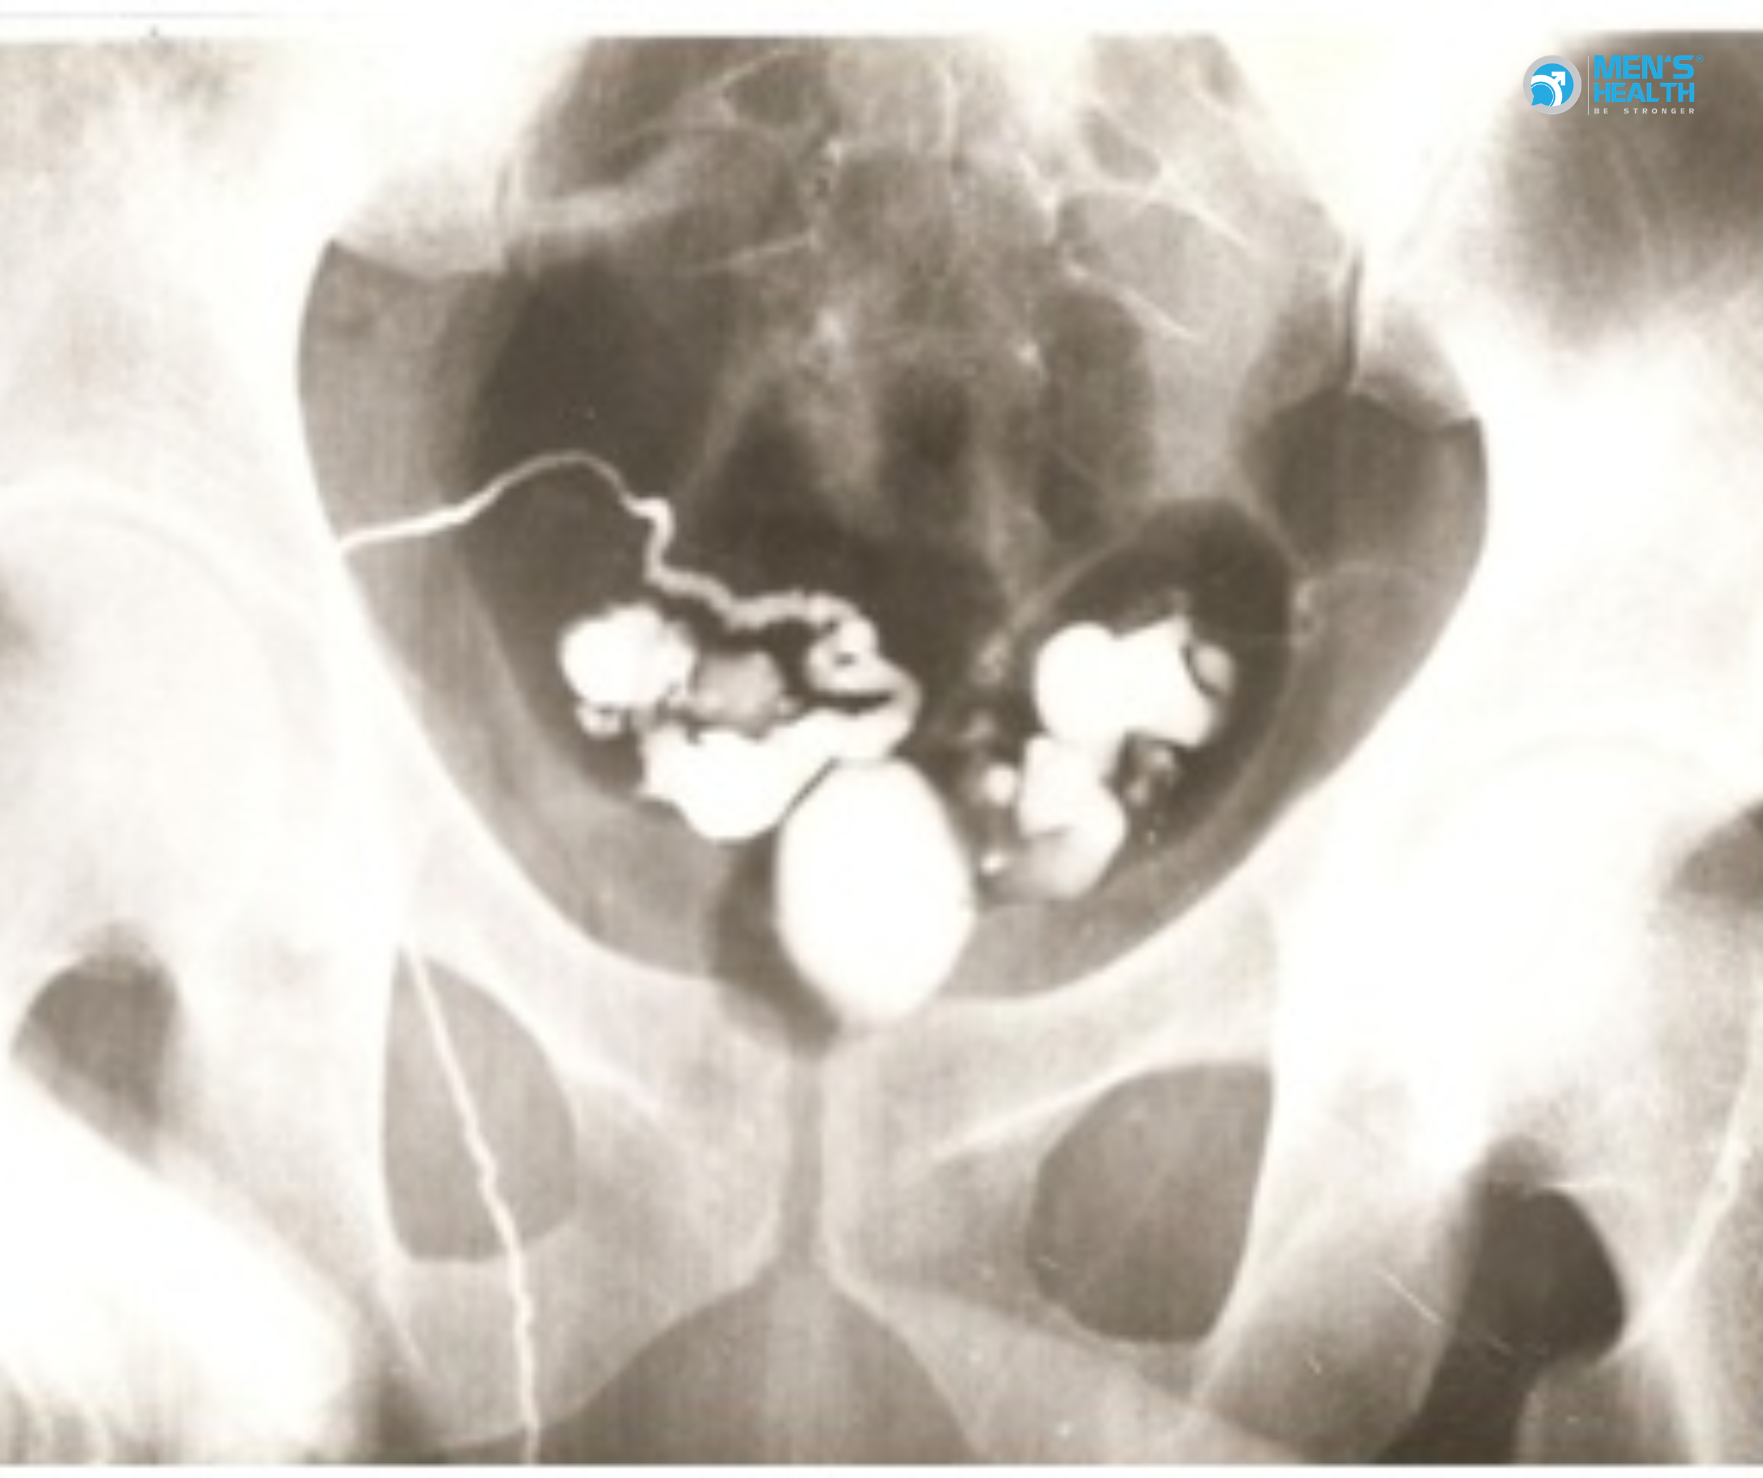

- Chụp ống dẫn tinh (vasography): xác định vị trí và mức độ tắc.

Silber (1989) báo cáo trên Journal of Urology rằng, trong nhóm 74 bệnh nhân OA sau phẫu thuật vùng bẹn, vasography cho phép xác định chính xác vị trí tắc ở 68 trường hợp (92%).